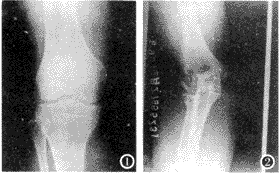

X线表现 腕关节、膝关节、肩关节、肘关节、踝关节各组成骨、手掌指骨、足趾骨等松质骨内均可见大小不等,分布不均,边缘清楚,两侧对称的圆形或椭圆形的致密斑点状骨质硬化灶,无骨膜反应及骨皮质增厚(图1、2)。股骨颈大小粗隆间、坐骨、耻骨、髂骨近骶髂关节处、骶椎骨、腰椎椎板均可见圆点状及部分融合成斑点状,条状大小不等(0.2~1.8cm)骨质硬化灶。颅骨、肋骨、椎体骨等未发现病灶。

图1 右膝关节股骨远端,胫腓骨近端见多个斑点状高密度影。

图2 右肘关节肱骨远端,尺桡骨近端见多个点状高密度影。